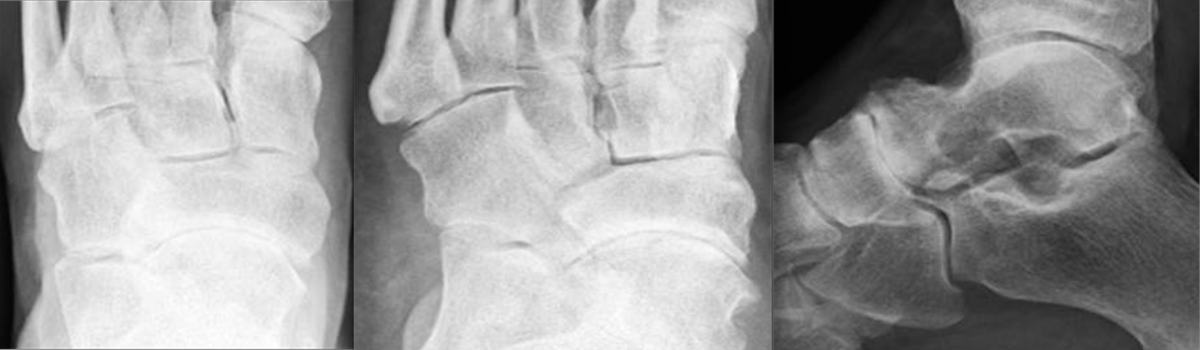

Another advancement in the development of locking plate technology is the addition of polyaxial or variable axial screw holes in the plate. This becomes extremely valuable when a surgeon is addressing a periarticular fracture, especially one that involves significant comminution or damage to the soft tissue envelope. These plates were designed to improve angular stability by allowing variable screw trajectory to the plate, thereby increasing the probability that the screw will be able to purchase good bone while avoiding articulating surfaces.